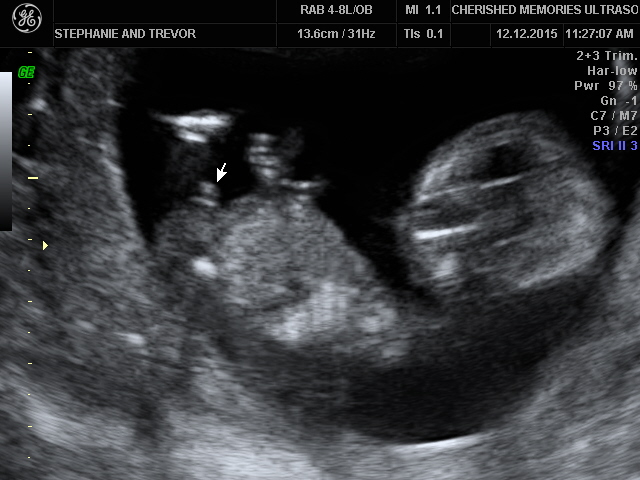

We had our elective gender scan at what was supposed to be 14.5 weeks but I royally screwed up the dates and ended up being 13 weeks exactly. They told me they'd try anyway....and the tech said it's a boy! I have a 1.5 year old son so I am falling in love with the idea of another boy...but sometimes I look at the pictures and I just don't see it. I mean, I see what I think is a penis, but it doesn't look attached to the body and the bottom part is very flat with maybe lines? And the one shot of the baby on its back with its willy just hanging all out there seems so impractical (and HUGE!) for 13 weeks. Is that even possible? With my son you could see a small bump in between his legs at 15 weeks, but not that big at all!! Is there a tech in this board or something that can help me out here?

• It seems early, I went at 14.4 weeks and they told me girl and I think they are right but I am still keeping it in the back of my mind that it could change. In my ultrasound the umbilical cord was between her legs but it was bigger then what boy parts would look like and she had flat lines there which is supposed to be the start of labia forming.

In your picture I cant really tell if what is supposed to be the boy parts is attached or not it could also be the umbilical cord. So I'm not really sure sorry but I would keep in mind that the gender might change at your 20 week ultrasound so I wouldn't go buying baby boy stuff just yet.